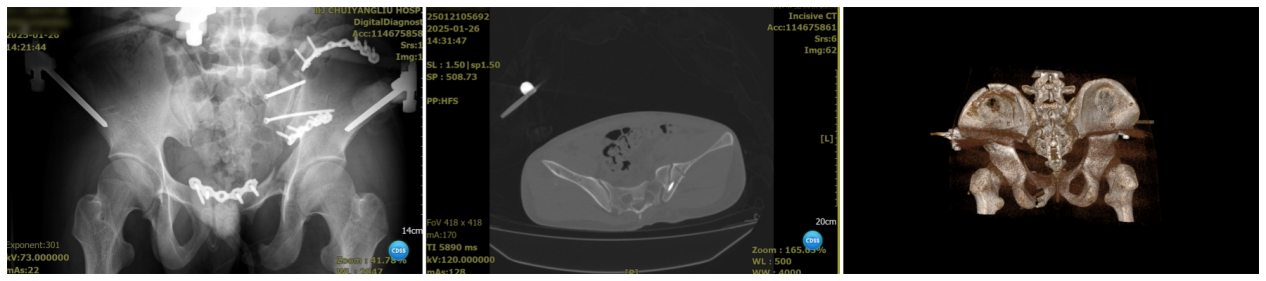

▲术后检查

术后患者转入ICU继续治疗,维持生命体征、纠正贫血。1天后患者平安度过危险期,转回8D普通病房继续接受恢复治疗。